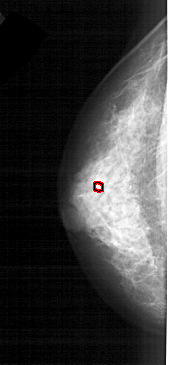

A_1609_1.LEFT_CC

LEFT_CC LINES 4006 PIXELS_PER_LINE 1861 BITS_PER_PIXEL 12 RESOLUTION 43.5 OVERLAY

FILE: A_1609_1.LEFT_CC.OVERLAY

TOTAL_ABNORMALITIES 1

ABNORMALITY 1

LESION_TYPE CALCIFICATION TYPE PLEOMORPHIC DISTRIBUTION CLUSTERED

ASSESSMENT 4

SUBTLETY 2

PATHOLOGY BENIGN

TOTAL_OUTLINES 1

BOUNDARY